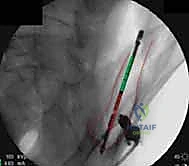

* المسامير الطبية (Screws): تُثبت الشرائح بالعظم، وتُستخدم أحياناً مسامير طويلة (Iliosacral Screws) لربط عظم الحرقفة بالعجز لضمان استقرار المفصل.

يتم الاستعانة بجهاز الأشعة السينية المتحرك داخل غرفة العمليات (C-arm Fluoroscopy) للتأكد من وضعية المسامير بدقة المليمتر، لضمان عدم اختراقها للأعصاب أو الأوعية الدموية.